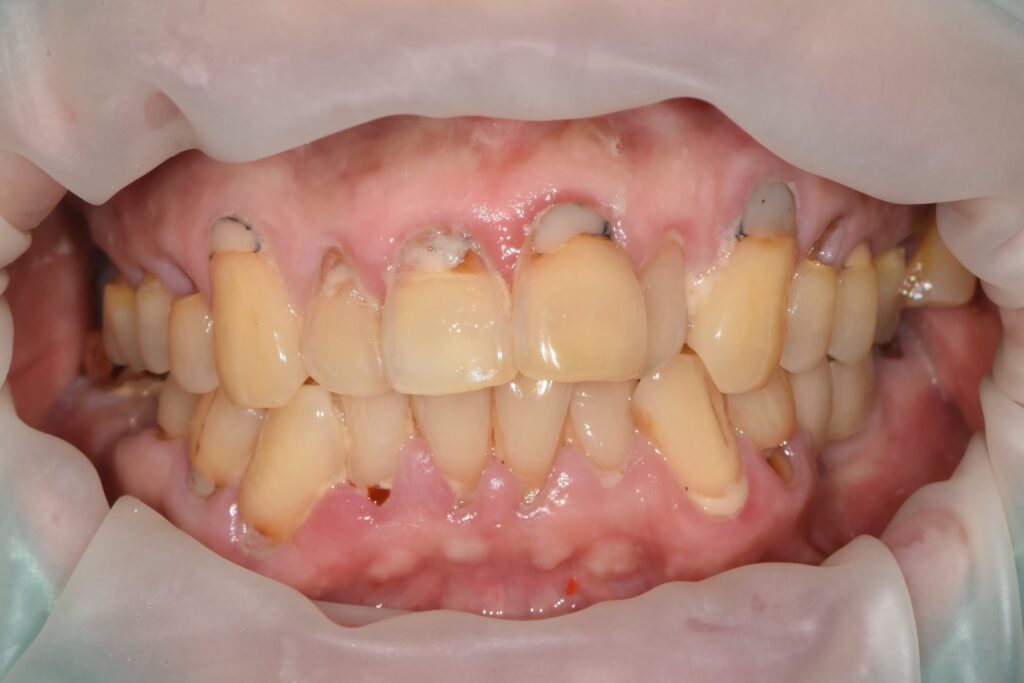

또한 파노라마 평가에서

전반적인 만성 치주염(수평적 골 소실) 소견이 함께 확인되어,

“임플란트만 심으면 끝”이 아니라 잇몸 컨디션을 안정화하면서 임플란트를 진행하는 장기 플랜이 필요했습니다.

이 시기에 환자분은 치주 상태가 전반적으로 좋지 않아,

임플란트 부위만 보는 것이 아니라 치석 제거·치주 소파술·치근활택술을 여러 차례 병행하며 잇몸 염증을 관리했습니다.

다만 이 환자분은 기본적으로 만성 치주염으로 인한 전반적인 치석/염증 재발 성향이 반복적으로 기록되어,

정기 내원 시마다 “잇몸이 다시 붓고 피가 난다”는 흐름이 나타났습니다.